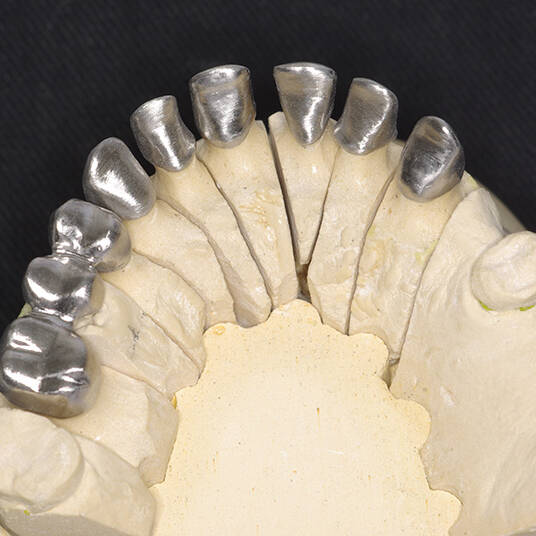

A reabilitação oral é um conjunto de tratamentos odontológicos que combina próteses dentárias, técnicas estéticas e terapias restauradoras. O principal objetivo desse procedimento é devolver ao paciente a capacidade de mastigar, falar e sorrir com confiança. Além disso, é fundamental para a saúde bucal, já que remove infecções e corrige problemas funcionais.

A reabilitação oral é um dos procedimentos mais completos da odontologia, envolvendo várias especialidades como prótese dentária, implantodontia e periodontia. Esta integração permite restaurar a saúde bucal de forma global, garantindo que o paciente recupere a função mastigatória, a harmonia estética e a saúde oral.